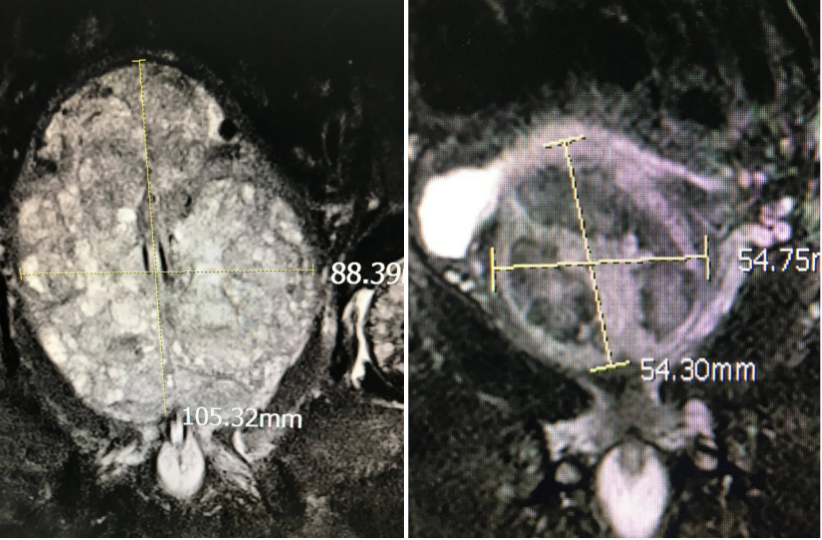

回到文章最初的问题:面对如此巨大的增生腺体和漫长的病史,即便是经验丰富的医生,也会认为传统的药物治疗已难有作为。但看到他如今的畅快,我们同样感到无比振奋。那么,PAE技术为何能“四两拨千斤”,解决这个“男”题?

图:通过栓塞增生部分萎缩(图为栓塞前和栓塞后一个月的对比)